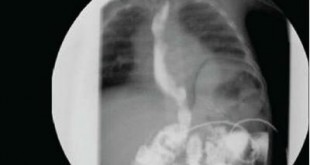

X quang thực quản cản quang với Barium (Barium swallow)

Trong khảo sát này, bạn uống một chất lỏng chứa Barium. Chất lỏng thường có hương vị trái cây giúp bạn dễ chịu khi uống. Bạn đứng trước một máy X quang và sẽ được chụp X quang trong khi bạn thực hiện nuốt chất lỏng này. Mục đích của khảo sát là để tìm các vấn đề ở thực quản như: hẹp thực quản, thoát vị hoành, khối u, trào ngược dạ dày thực quản, rối loạn nuốt,… Thông thường bạn sẽ được đề nghị không ăn uống một vài giờ trước khi làm khảo sát này. Một khảo sát X quang thực quản cản quang với Barium mất khoảng 10 phút.